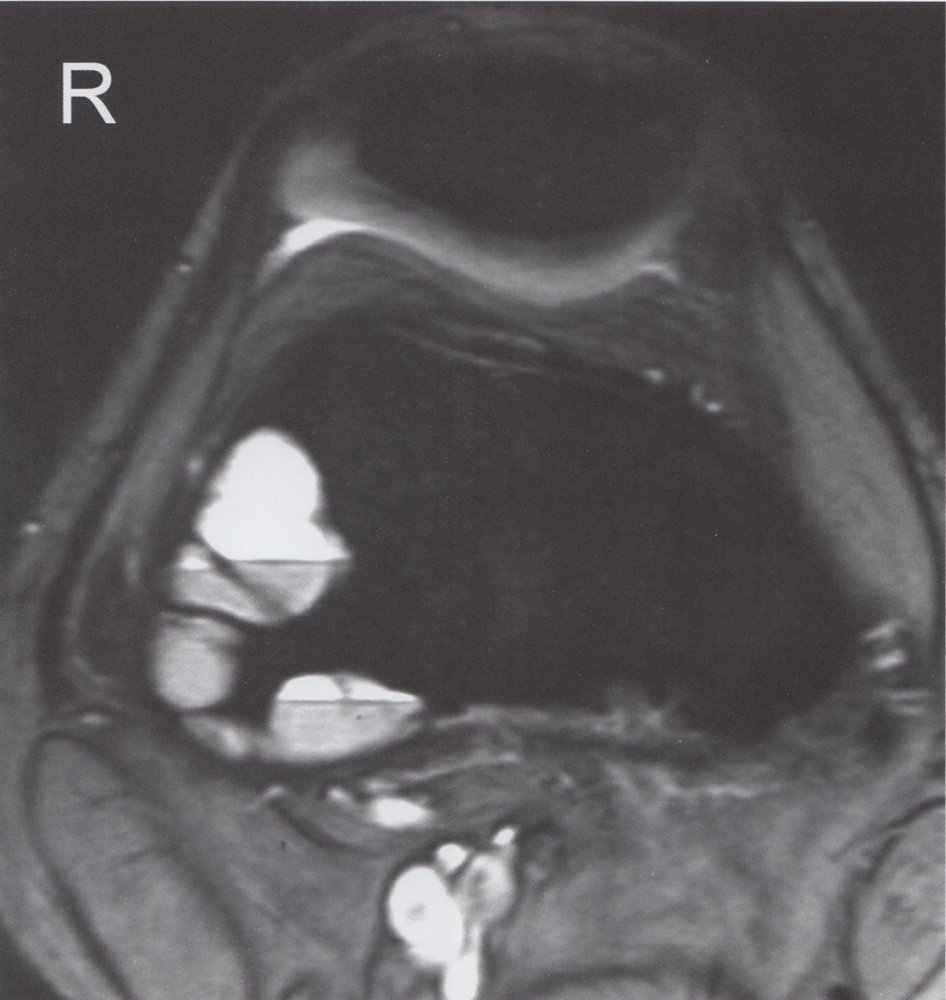

• Description

• Osteolytic lesions; usually septated, blood-filled cysts

• Idiopathic (primary aneurysmal bone cyst) or secondary to malignant or other benign bone diseases (secondary aneurysmal bone cyst)

• Epidemiology: peak incidence between 10 and 20 years

• Clinical features

• Common sites are the spine and the metaphysis of the femur and tibia.

• Usually asymptomatic; local pain and swelling may occur

• Pathological fracture: often the first sign

• Diagnostics

• X-ray: metaphyseal, osteolytic lesion with sclerotic margins

• MRI : septated, blood-filled lesions, with typical fluid-fluid levels.

• Treatment: surgical curettage and bone grafting

• Prognosis: high risk of recurrence